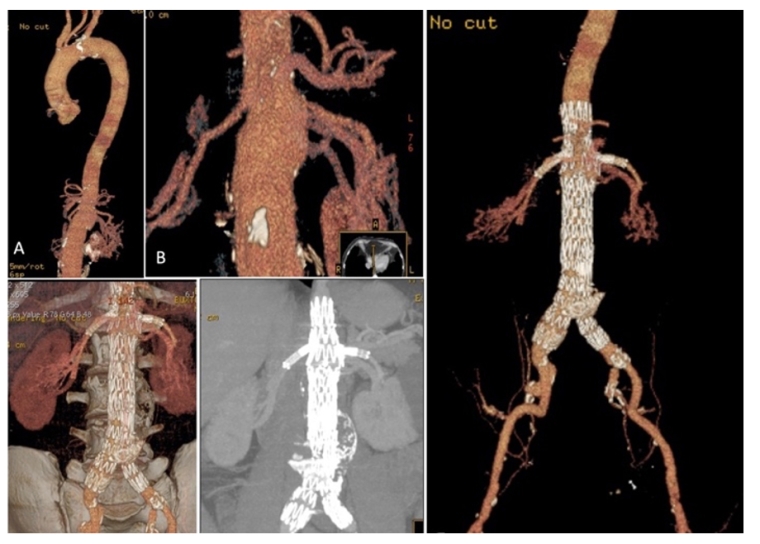

Custom-made fenestrated/branched grafts to accommodate visceral arterial ostia and parallel-graft technology allow proximal extension of the aortic sealing and fixation by incorporating the renal and visceral arteries preserving their flow [4]. They extend the applicability of EVAR to short neck AAA, juxtarenal or pararenal AAA. Figure 2A shows the case of a patient with a pararenal aortic aneurysm successfully treated with double fenestration for the renal arteries and a scallop for the superior mesenteric artery, without complications and full exclusion of the aneurysm eight years later.

229_Fernandes_Figure 2A_Abdominal aortic aneurysms.jpg

Distal sealing is usually obtained at the common iliac arteries provided there is no iliac dilatation. Extension of the graft limb to the external iliac artery with exclusion of the hypogastric artery increases the risk of pelvic and bowel ischaemia and later buttock claudication and sexual dysfunction, especially if bilateral hypogastric exclusion was performed. Spinal cord ischaemia may occur in this setting, but it is a very rare event in abdominal aneurysm repair. Branched grafts to the hypogastric arteries - iliac branched device (IBD) - overcome this limitation preserving both external iliac and hypogastric arterial flow [1].  Commercially available IBDs provide safe and durable procedures. This is documented in Figure 2B showing a severely diseased patient with complex aneurysmal anatomy requiring exclusion of a 9 cm diameter left iliac aneurysm and an IBD on the right iliac axis for a smaller iliac aneurysm, preserving flow in the distal hypogastric artery.